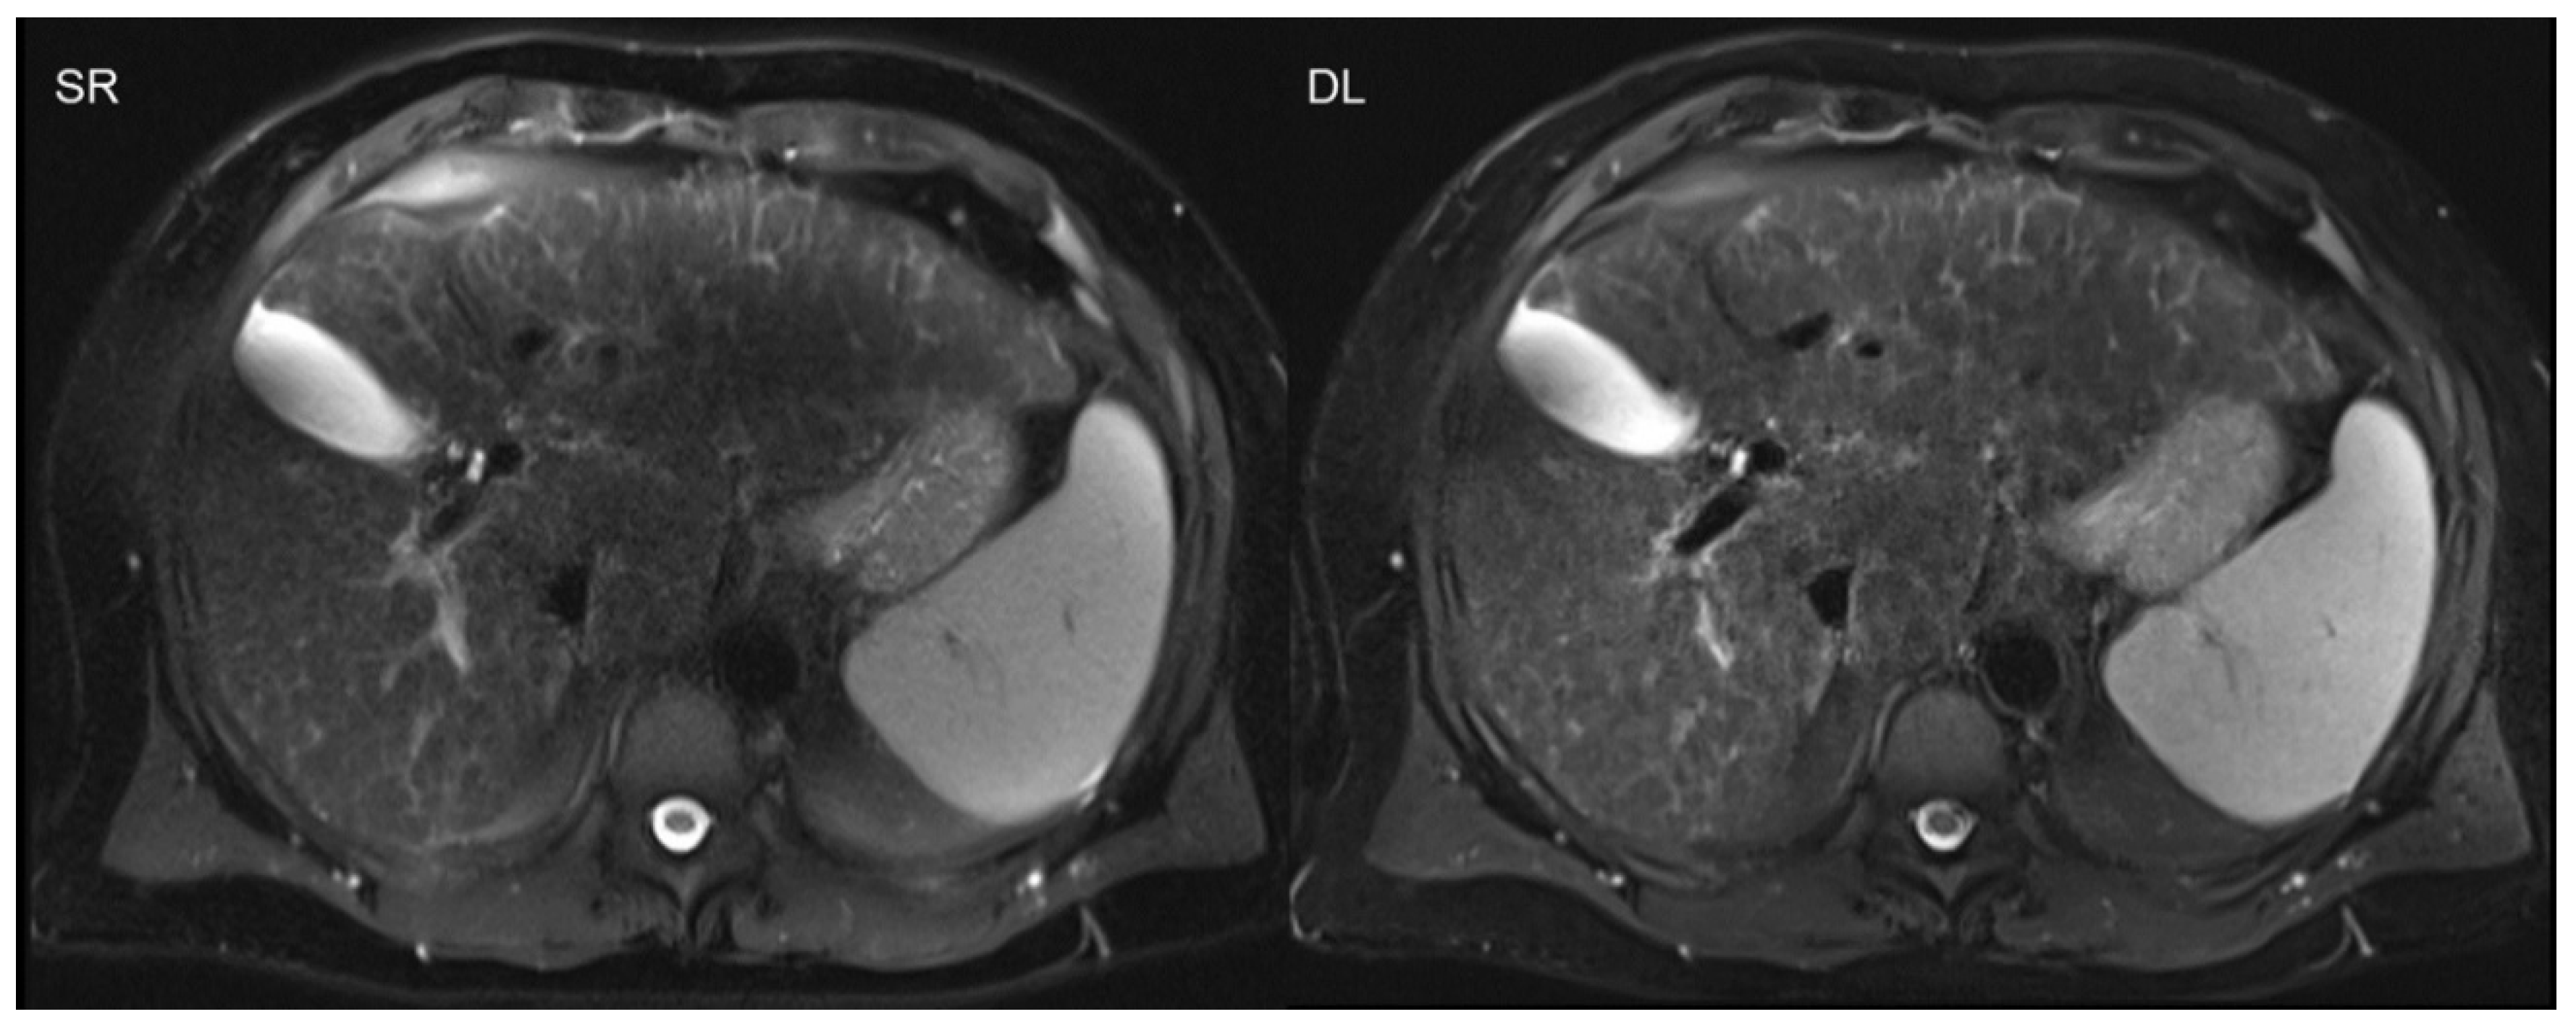

- Almansour, H.; Gassenmaier, S.; Nickel, D.; Kannengiesser, S.; Afat, S.; Weiss, J.; Hoffmann, R.; Othman, A.E. Deep Learning-Based Superresolution Re-construction for Upper Abdominal Magnetic Resonance Imaging: An Analysis of Image Quality, Diagnostic Confidence, and Lesion Conspicuity. Investig. Radiol. 2021, 56, 509–516. [Google Scholar] [CrossRef] [PubMed]

- Gassenmaier, S.; Afat, S.; Nickel, D.; Kannengiesser, S.; Herrmann, J.; Hoffmann, R.; Othman, A.E. Application of a Novel Iterative Denoising and Image Enhancement Technique in T1-Weighted Precontrast and Postcontrast Gradient Echo Imaging of the Abdomen: Improvement of Image Quality and Diagnostic Confidence. Investig. Radiol. 2021, 56, 328–334. [Google Scholar] [CrossRef] [PubMed]

- Gassenmaier, S.; Herrmann, J.; Nickel, D.; Kannengiesser, S.; Afat, S.; Seith, F.; Hoffmann, R.; Othman, A.E. Image Quality Improvement of Dynamic Contrast-Enhanced Gradient Echo Magnetic Resonance Imaging by Iterative Denoising and Edge Enhancement. Investig. Radiol. 2021, 56, 465–470. [Google Scholar] [CrossRef]